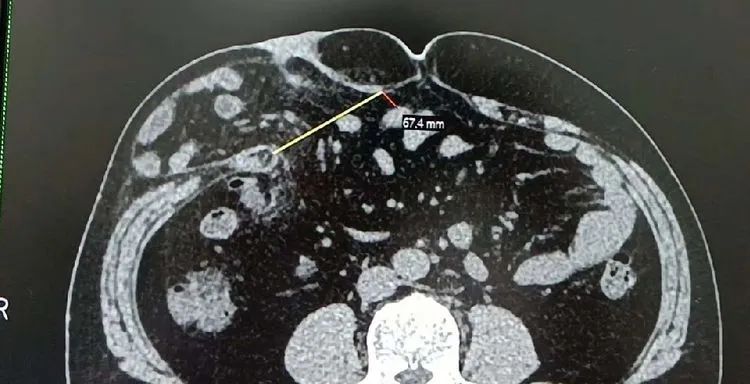

因“反复腹痛1年余,再发1周”,黄师傅(化名)前往医院就诊,查体:腹平,未见肠型及蠕云波,右季肋区饱满,可触及一5*7cm左右质软包块,触痛阴性,腹软,肝脾肋下未及,剑突下及脐周深压不适,余腹无明显压痛、反跳痛及肌卫,Murphy症(一)。CT可见:右腰部软组织变薄,部分脂肪组织疝入皮下,疝口宽约74mm。影像学诊断:右腰部脂肪疝。